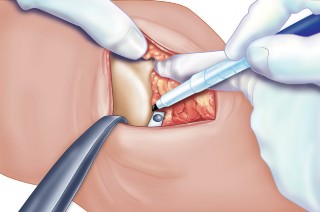

2. الوضع الجراحي والتعرض

- الوضع: يُوضع المريض في وضع الاستلقاء (Supine positioning) مع وضع كيس رمل أسفل الركبة أو حامل للساق يسمح بثني وفرد الركبة. يجب أن يكون الوضع مماثلاً لوضع جراحة TKA، مع استعداد لتحويل الإجراء إلى TKA إذا لزم الأمر.

- العاصبة (Tourniquet): تُستخدم عاصبة وتُوضع في أعلى الفخذ لتقليل النزيف.

-

الشق الجراحي:

يُستخدم شق طولي في الجانب الإنسي (الداخلي) من الركبة. يجب أن يكون الشق كبيرًا بما يكفي لتوفير رؤية جيدة للمفصل الرضفي الفخذي وإمكانية التحويل إلى TKA.

- فتح المفصل (Arthrotomy): يكون الفتح خطيًا وموازياً لألياف الوتر الرضفي، ويمتد إلى عظم الظنبوب وإلى الجزء السفلي من الرضفة.